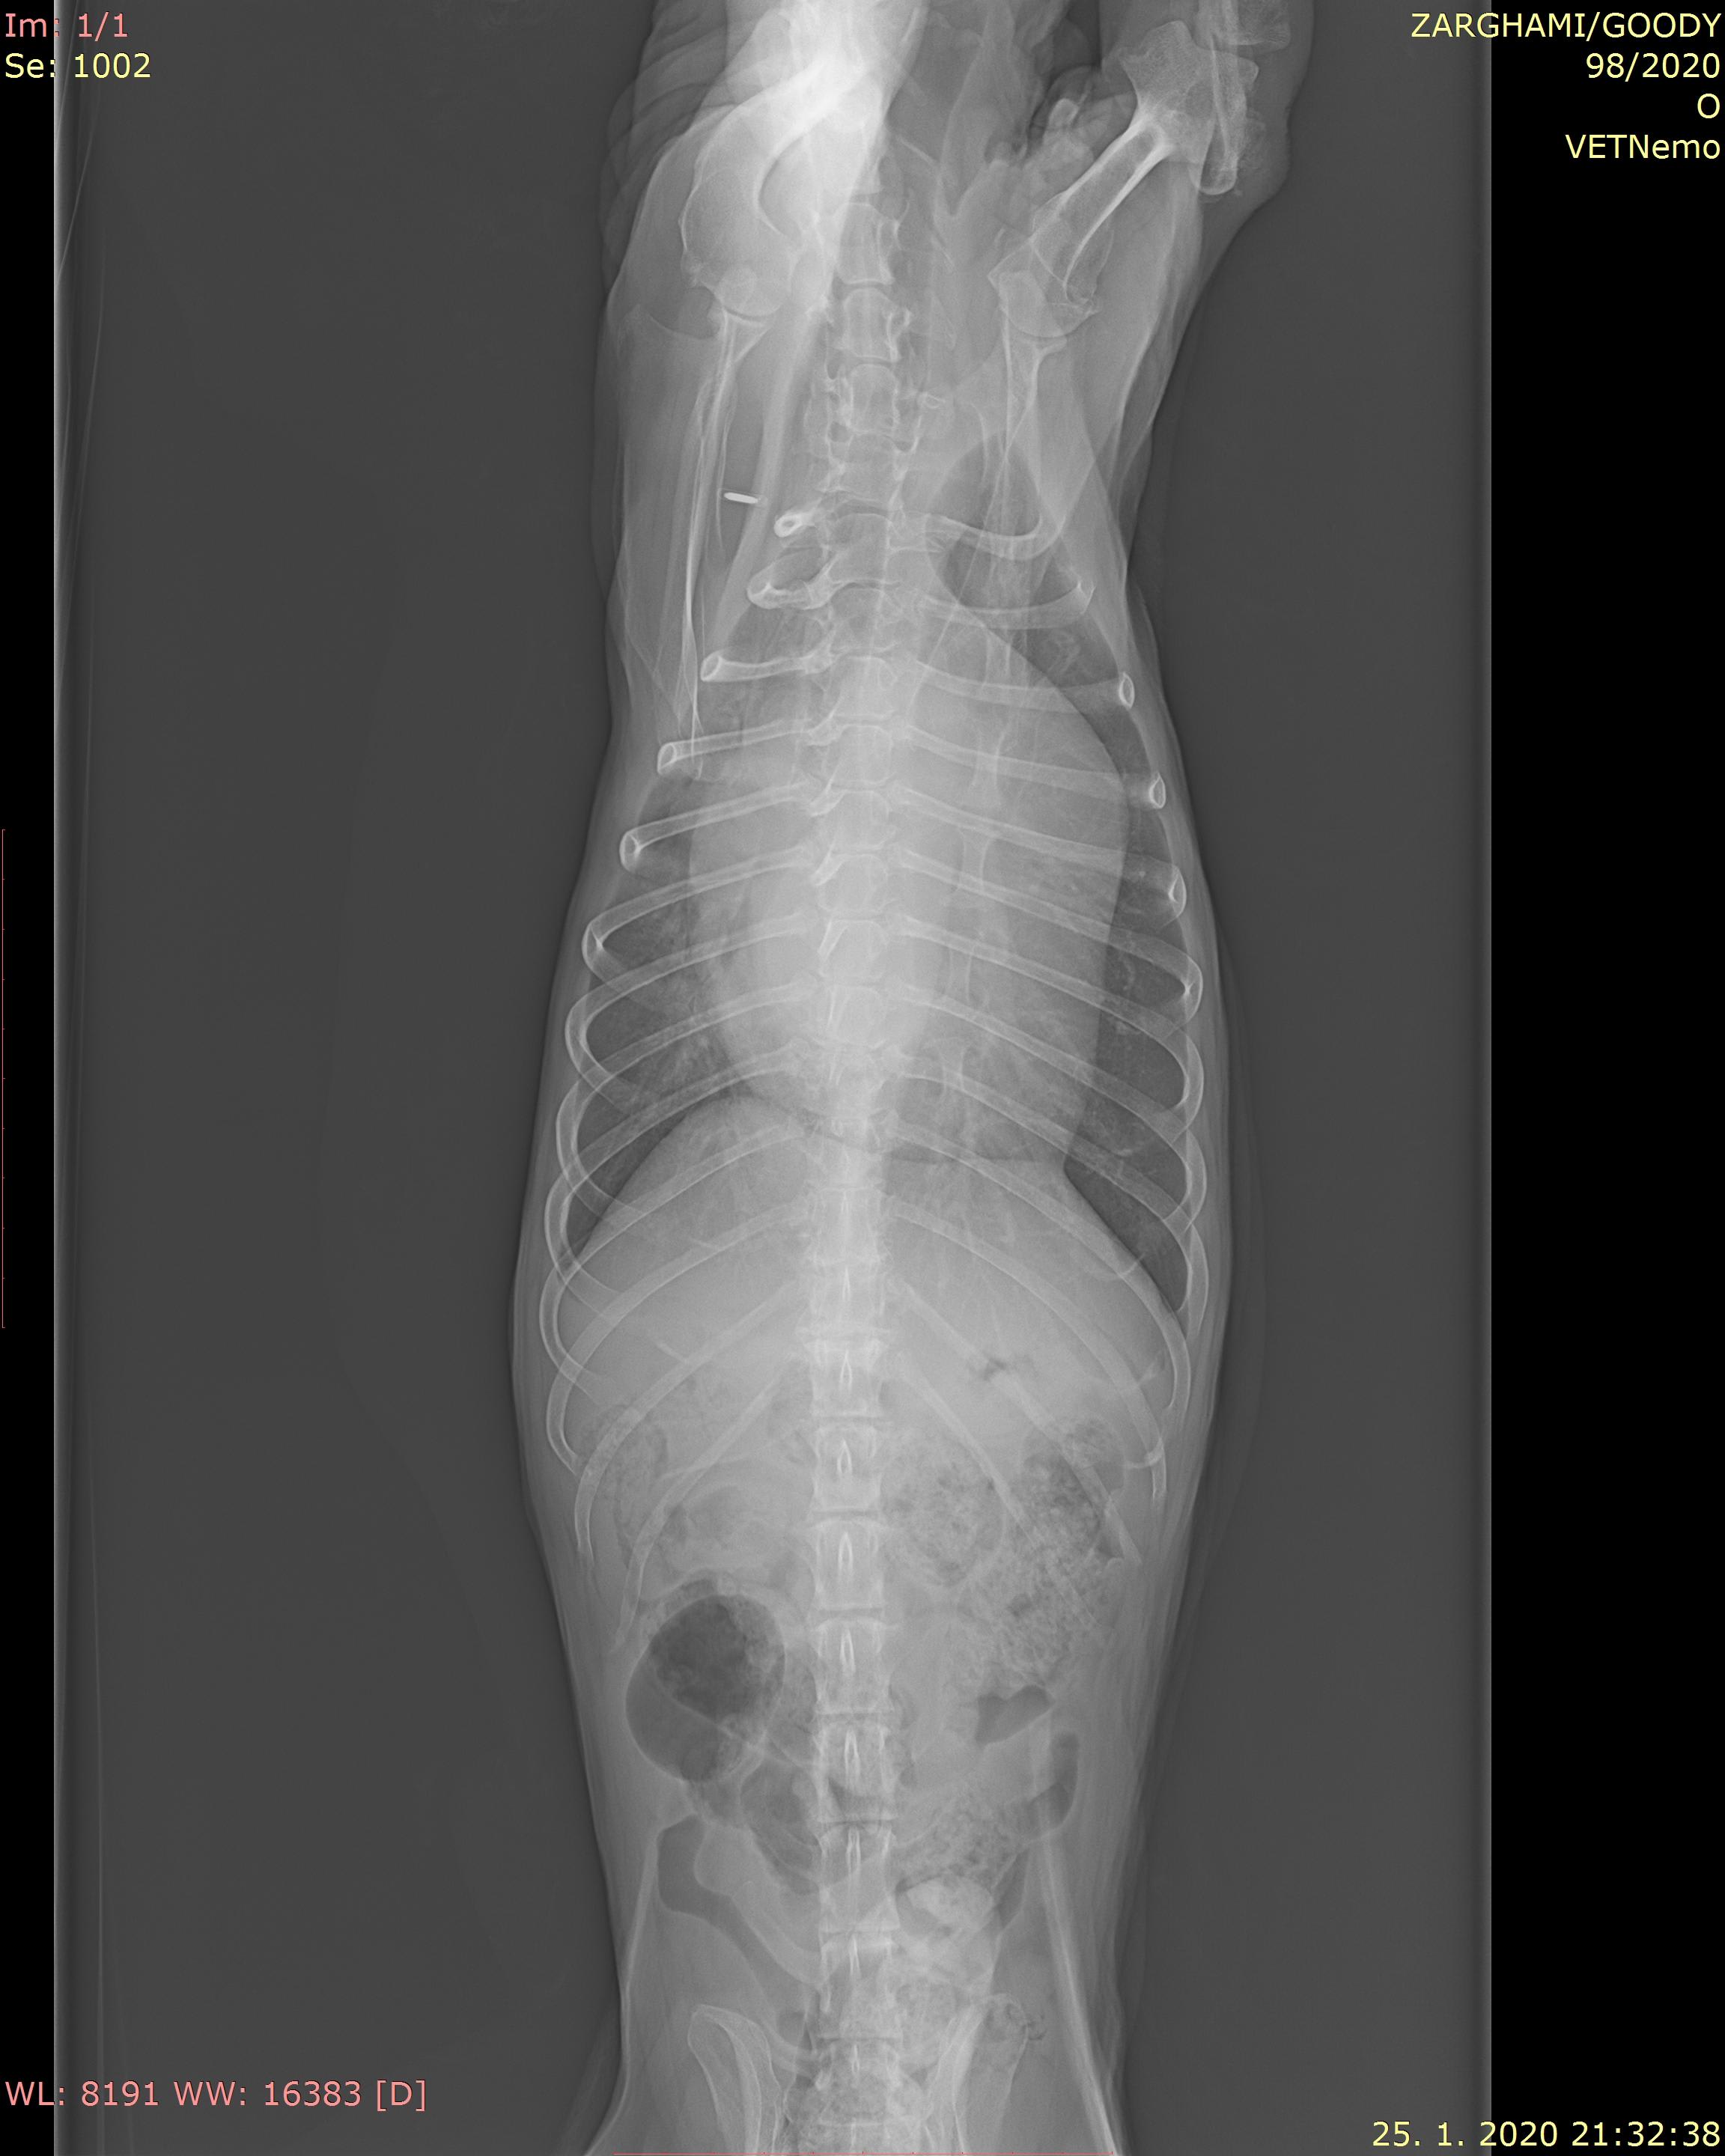

Hello there, I have a terrier senior dog, he is 15 and 8 month,he is suffering from heart failure, he uses several medicine like vetmedin 1.25mg , cordarone200mg 1 quarter morning and one quarter in the evening, upcard 0.75mg 1 in the morning and half in the evening and virospiron 25mg 1quarter a day,but since previous week he starts frequent coughing ,he has a sever shortness breathing tonight and drinking water more. here is tonight X-ray the vet said there is no pulmonary.please advice me

Your dog has severe heart enlargement. For this reason, it is pressing his windpipe (trachea) upward and causing a narrowing which is the likely cause of his cough. Unfortunately, there's no way to prevent this. Ideally, you would keep him as quiet as possible and minimize his activity/stress. Your vet is correct, it doesn't look like he has pulmonary edema. You may want to consider medication to keep him more relaxed to prevent excessive coughing.